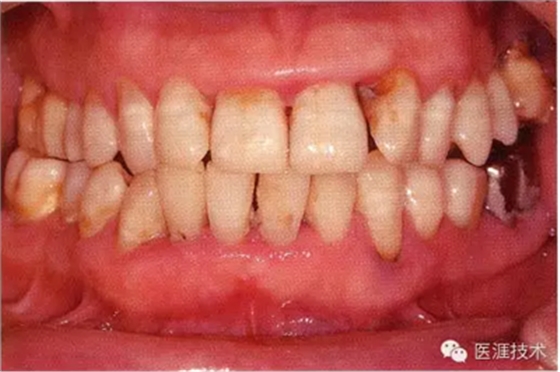

55歲牙周炎男性的臨床照片

55歲男性抽煙患者(1天20支、抽煙35年)。菌斑控制得不好。通過牙周探診,全頜有4~9mm的牙周袋,有1~3度的根分叉部病變。通過X光片觀察,上頜前牙中度牙槽骨吸收,其他地方有中度牙槽骨吸收。受吸煙影響,牙齦纖維性肥厚,呈紅黑色。牙齦幾乎沒有浮腫和發(fā)紅,所以這個病例是從外觀上無法預測病癥嚴重程度的病例。